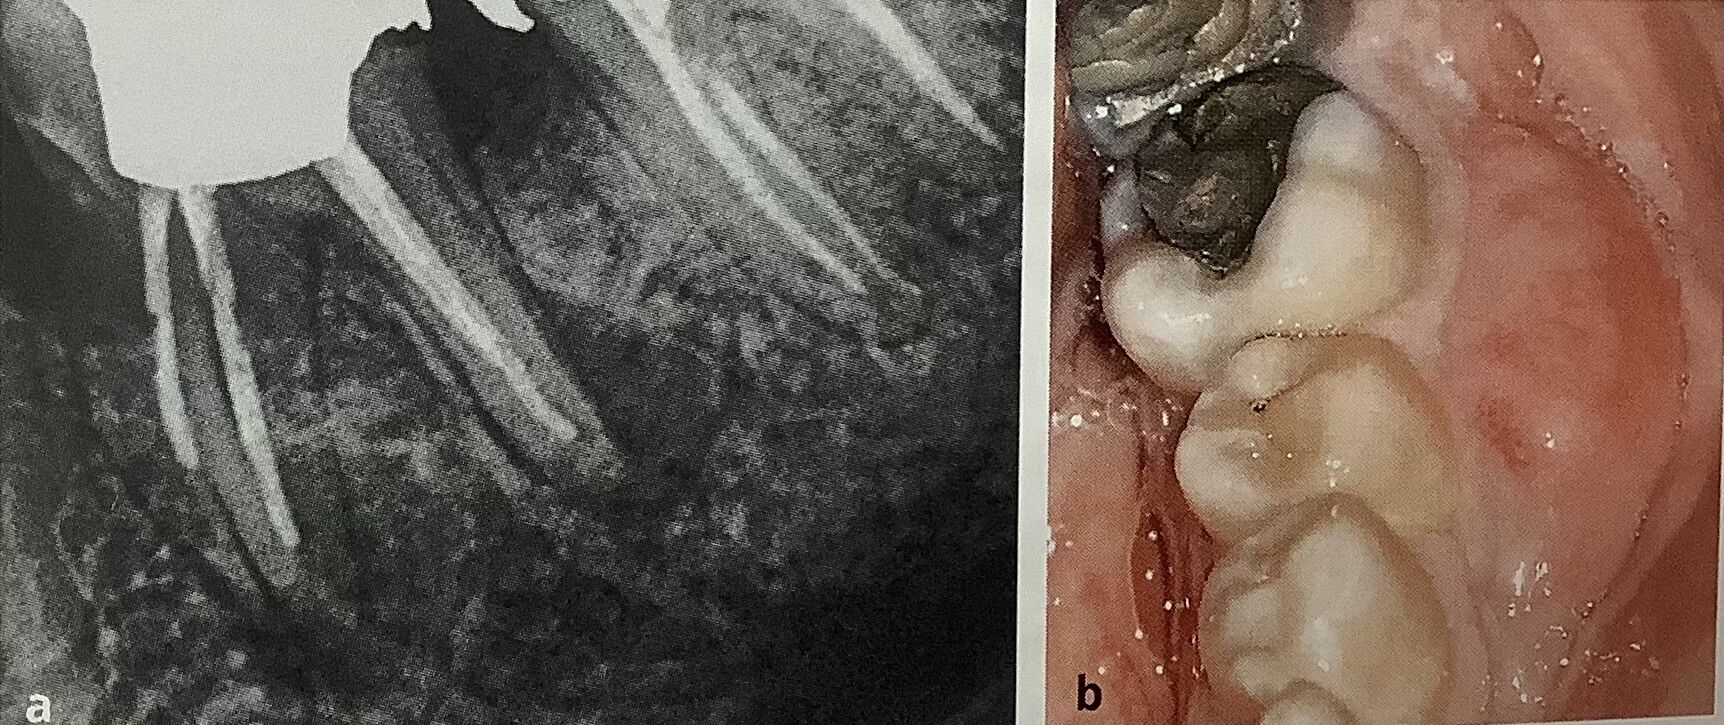

レントゲンで白く見えるのが詰め物や被せ物。

その境目に黒くなっているので、虫歯がまた出来ちゃった。

下の歯ではセラミックが欠けています。

一本には根っこに黒いカゲも見えます。

白いクスリが短くて、根っこにも黒いカゲが。

根元の歯ぐきも腫れています。